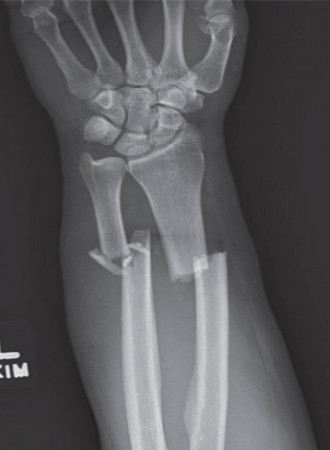

Standard orthogonal imaging, including true anteroposterior (AP) and lateral radiographs of the forearm, elbow, and wrist, is mandatory. The integrity of the PRUJ and DRUJ must be critically assessed to rule out associated Monteggia or Galeazzi fracture-dislocations.

Contralateral templating is a cornerstone of preoperative planning. Radiographs of the uninjured forearm provide an individualized template of the patient's native radial bow magnitude and location. In complex comminuted fractures or established malunions, computed tomography (CT) with three-dimensional reconstructions is highly recommended. Advanced planning software can mirror the contralateral intact radius, allowing for precise calculation of the required osteotomy angles or the degree of plate contouring necessary to restore the native anatomy.